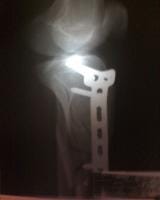

Doctor mi nombre es soy de la ciudad de Caracas Venezuela tengo 19 años de edad queria hacerle unas cuantas preguntas con respecto a mi fractura como lo indica el titulo una fractura metafisiaria de tibia izquierda el dia 01/01/09 ingrese al hospital y me indicaron que tenia que quedar internado hospitalizado durante 1 mes espere la operacion el dia 28/01/09 me operaron se me realizo una reduccion mas fijacion interna con placa lcp 4,5++ ingerto oseo en fisura de tibuia izquierda evolucione de forma satisfactoria y fui dado de alta el dia 30/01/09 acudi a control en el hospital pero devido a que me plantearon retiro de tornillo proximal, les plantie que necesitaba consultar con otros traumatologos y me indicaron que no era necesario devido a eso me retire del hospital y acudi a otro centro cree usted que sea el tipo de placa indicado el que me colocaron?.

Durante este tiempo los demas traumatologos me decian que no era necesario ya que la palca no presentaba rechazo, pero con respecto a eso doctor queria hacerle una pregunta tengo mi pierna hinchada en la parte inferior de la placa es visible la placa se puede palpar los tornillos mucho mas que antes.. Hace aproximadamente empeze a afincar sin amuletas y camino bien pero al caminar mucho se me hincha la pierna y me duele mucho espero que me ayude tengo algunas fotos que se las dejare a continuacion para que usted opine al respecto tengo tiempo que no me tomo algunas placas pero recientemente me hare una.. La cicatriz presenta una protuberancia al afincar solo se ve la protuberancia pero al dejar de afincar desaparece como una pelota que piensa usted al respecto? ¿Esto me ha sido un problema devido a que no he trabajado devido a que se me complica usted cree que pueda estar presentando un rechazo de la placa? ¿Termine mis terapias efectivamente y se me plantea reanudarlas usted cree que sea indicado? O ir al gimnacio a ejercitar la pierna los musculos.. Espero su pronta respuesta muchas gracias dr..